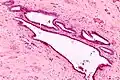

High magnification micrograph of endosalpingiosis, showing the characteristic cystic spaces lined by a simple epithelium with cilia. H&E stain.

It is characterized by cysts with tubal-type epithelium (e.g. ciliated epithelium) surrounded by a fibrous stroma. It is not often associated with hemorrhage.

Endosalpingiosis is occasionally found in lymph nodes, and may be misinterpreted as an adenocarcinoma metastasis.[5]